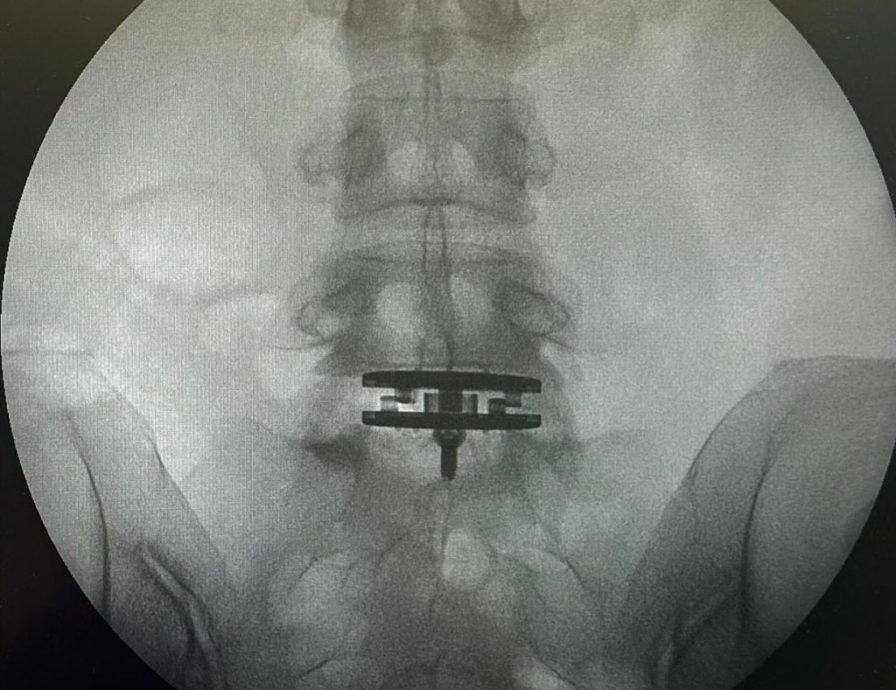

(香港27日讯)陈奕迅上个月初打球中暑晕倒,并撞伤下巴缝30多针,老婆徐濠萦则在月尾透露进行了椎间盘置换手术,近日她就提到自己的康复情况。

徐濠萦多年来受腰椎间盘突出而受背痛煎熬,上个月她透露在医生建议下进行了手术。近日她和女儿陈康堤到上海扫货,看来康复得不错。25日她就发文表示:“很多人问我:‘康复十分之快啊!’其实算是很好,可以走路,但现在不能拿太重的东西,也不能弯腰,最漫长的是不能跑步6个月,所以只能慢行,手术后第一次步行了1万步!康复中不影响继续扮美和享受美食!”